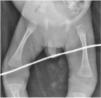

The findings of blood tests were reactive chemiluminescent immunoassay for detection of anti-Treponema pallidum antibodies (25.8 S/CO), anaemia (haemoglobin, 10g/dL), a leukocyte count of 9.4×103/mL, thrombocytopenia (95×103/mL), hypoglycaemia (58mg/dL), transaminasaemia (AST 554 U/L, ALT 135 U/L) with direct hyperbilirubinaemia (3.7mg/dL), hypoalbuminaemia (1.3g/dL) and an undetectable HIV viral load, and the radiographs evinced periostitis in the long bones (Fig. 3). Examination of a lumbar puncture sample revealed hypoglycorrhachia (28mg/dL), hyperproteinorrhachia (59mg/dL), sin pleocytosis y VDRL reactivo. The VDRL test in the mother was reactive (1:64).